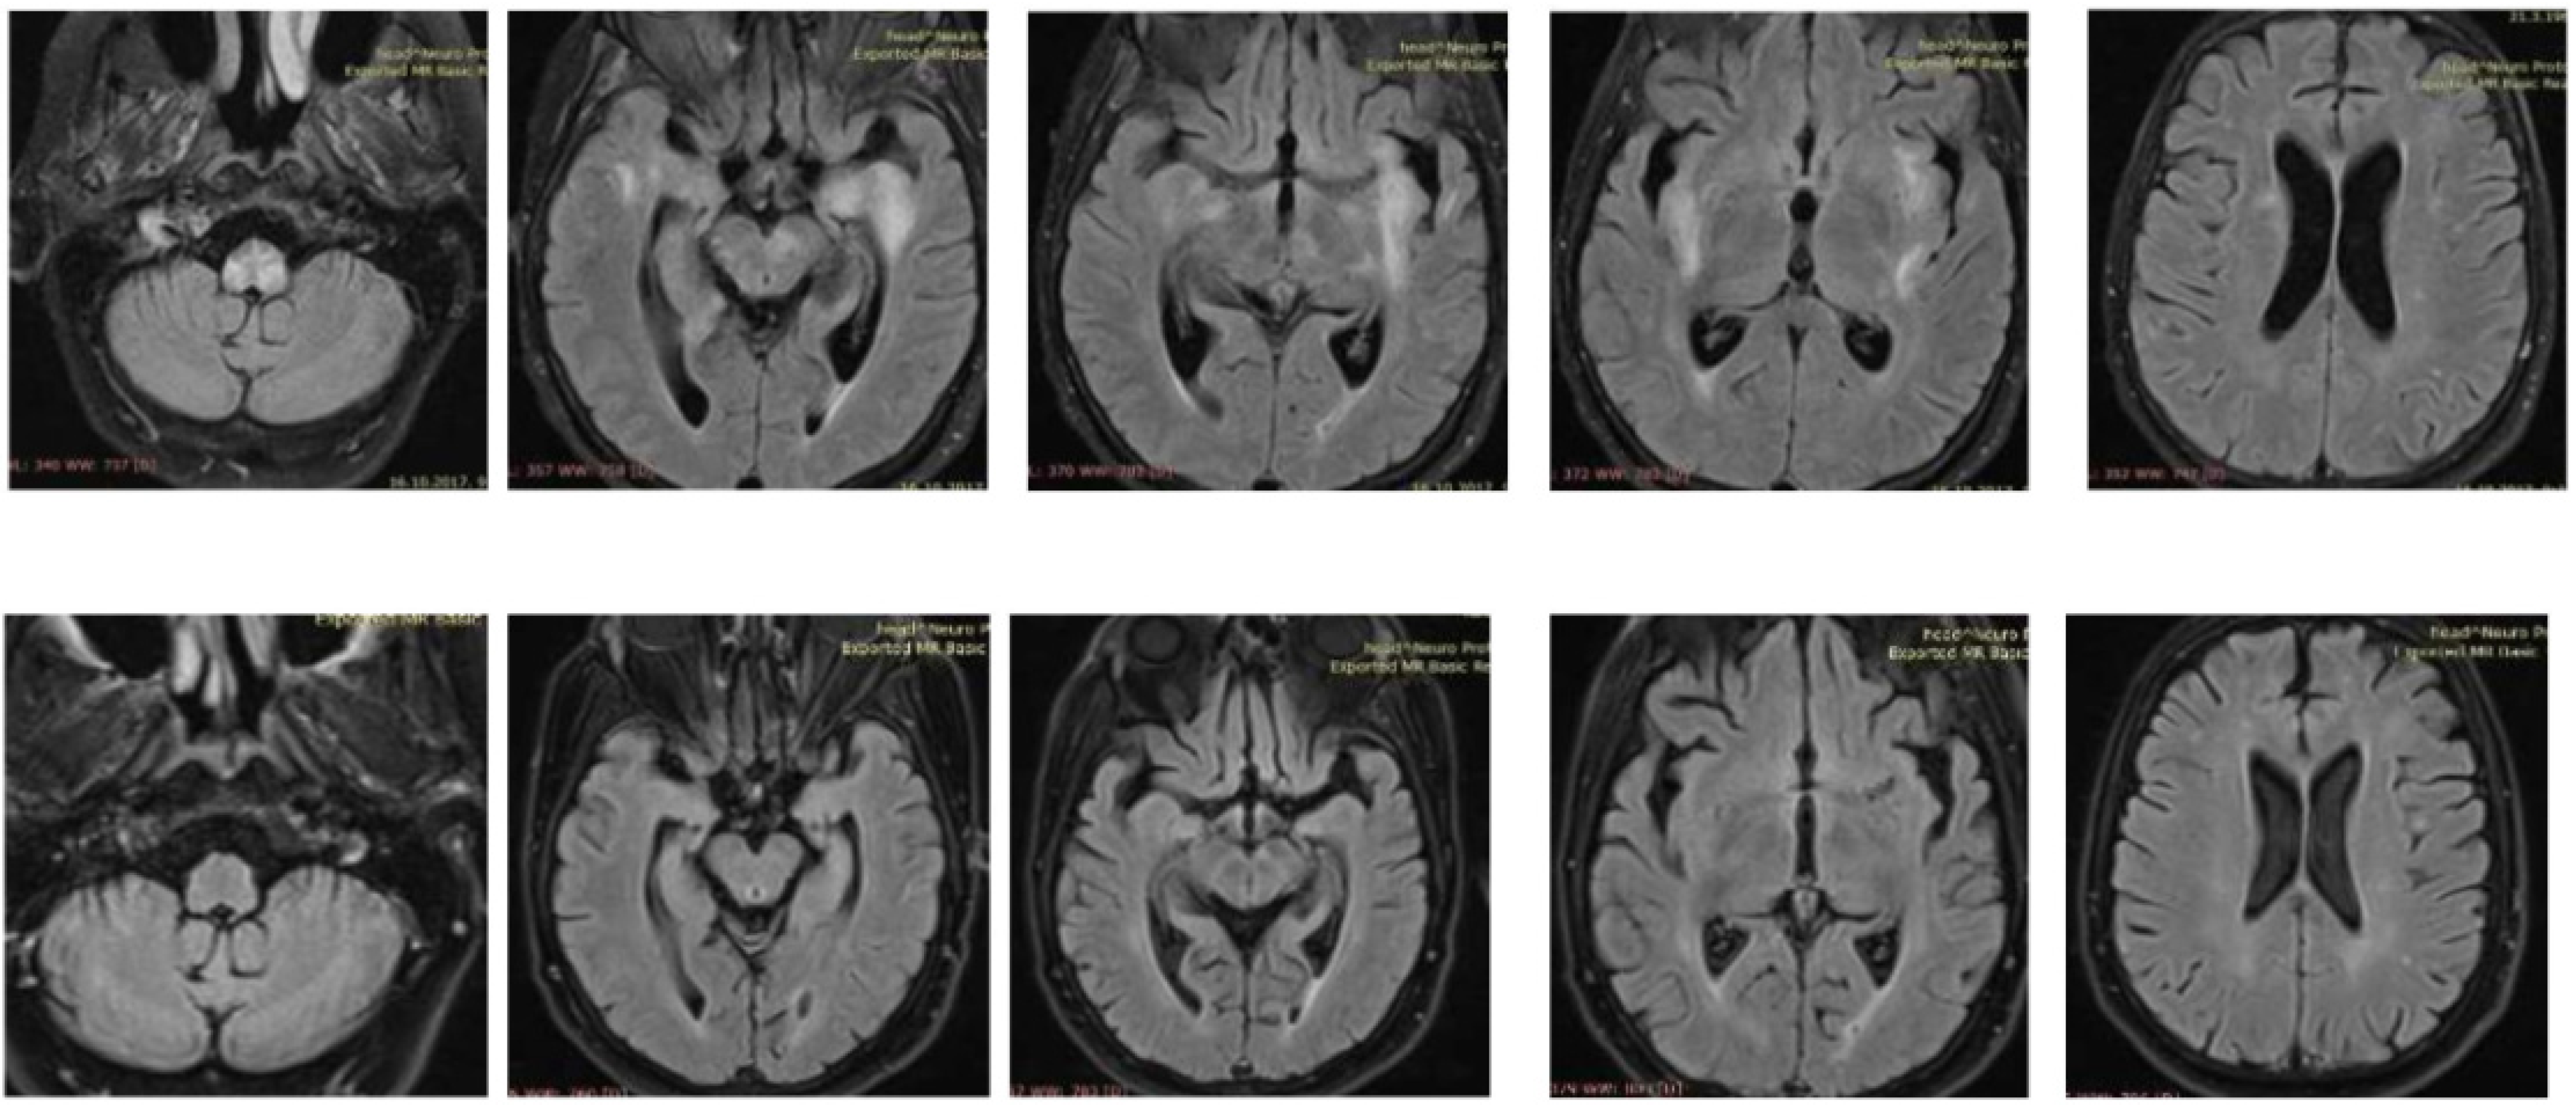

A 57-year old immunocompromised Caucasian woman with a diagnosis of SLE in stable remission for the last nine years and treated with low dose prednisone was admitted to the Internal Medicine Ward because of a poor general condition lasting for seven days and weakness in the right leg without sensory deficit lasting for two days. During that time, she became disorientated and confused, while meningeal signs were negative. Laboratory tests showed a sedimentation rate of 26 mm/h, leucocytes 3.9 × 109/L with neutrophilia, erythrocytes 4.38 × 1012/L with thrombocytopenia of 125 × 109/L, mild liver lesion with aspartate aminotransferase (AST) 43 U/L, and alanine aminotransferase (ALT) 71 U/L. C3 and C4 complement components were normal, as well as immunoglobulins level (IgA 0.91 g/L, IgG 10.1 g/L, and IgM 1.67 g/L). Antiphospholipid antibodies were positive (aCL-IgM 69.1 MPL/mL, aCL-IgG 88.8 GPL/mL), ANA titar (IIF) was 1:1280, and dsDNA (ELISA) 52 IU/mL (normal < 30 IU/mL). An urgent brain MSCT was performed and showed discrete hypodense lesions of the left perinsular and hippocampal region. Due to the previous medical history, clinical presentation and initial imaging findings, central nervous system (CNS) lupus, and subacute ischemic cerebrovascular disease were suspected. Follow-up CT after 5 days showed a new lacunar hypodense lesion in the left cerebellar peduncle. Next, MR angiography was performed excluding signs of vascular anomalies, ischemia, and vasculitis. In the second week, the patient showed further deterioration of clinical symptoms with a decrease in the leucocyte count (L 2.7 × 109/L), normocytic anaemia (hemoglobin 109 g/L), and thrombocytopenia (platelets 92 × 109/L). C3 was 0.83 g/L and C4 was normal. Brain MRI in the second week of hospitalization revealed the full extent of brain impairment: multiple parenchymal supratentorial and brainstem demyelinating lesions on T2 and FLAIR sequences without postcontrast enhancement on T1WI (Figure 1).

The patient‘s neurological status gradually improved. At the discharge, almost a month after admission, the patient was completely conscious with improved right leg paresis. Follow-up brain MRI, three weeks after the initial one, revealed partial regression of previously described demyelinating lesions. Further, a follow-up clinical examination 6 months after hospitalization showed mild right leg paresis and complete MRI regression of demyelinating lesions (Figure 1) Our patient had no similar recurrent attacks since.

Figure 1. Brain MRI: multiple parenchymal supratentorial and brainstem demyelinating lesions on T2 and FLAIR sequences without postcontrast enhancement on T1WI (upper row); follow-up MRI six months after hospitalization showing complete regression (bottom row).